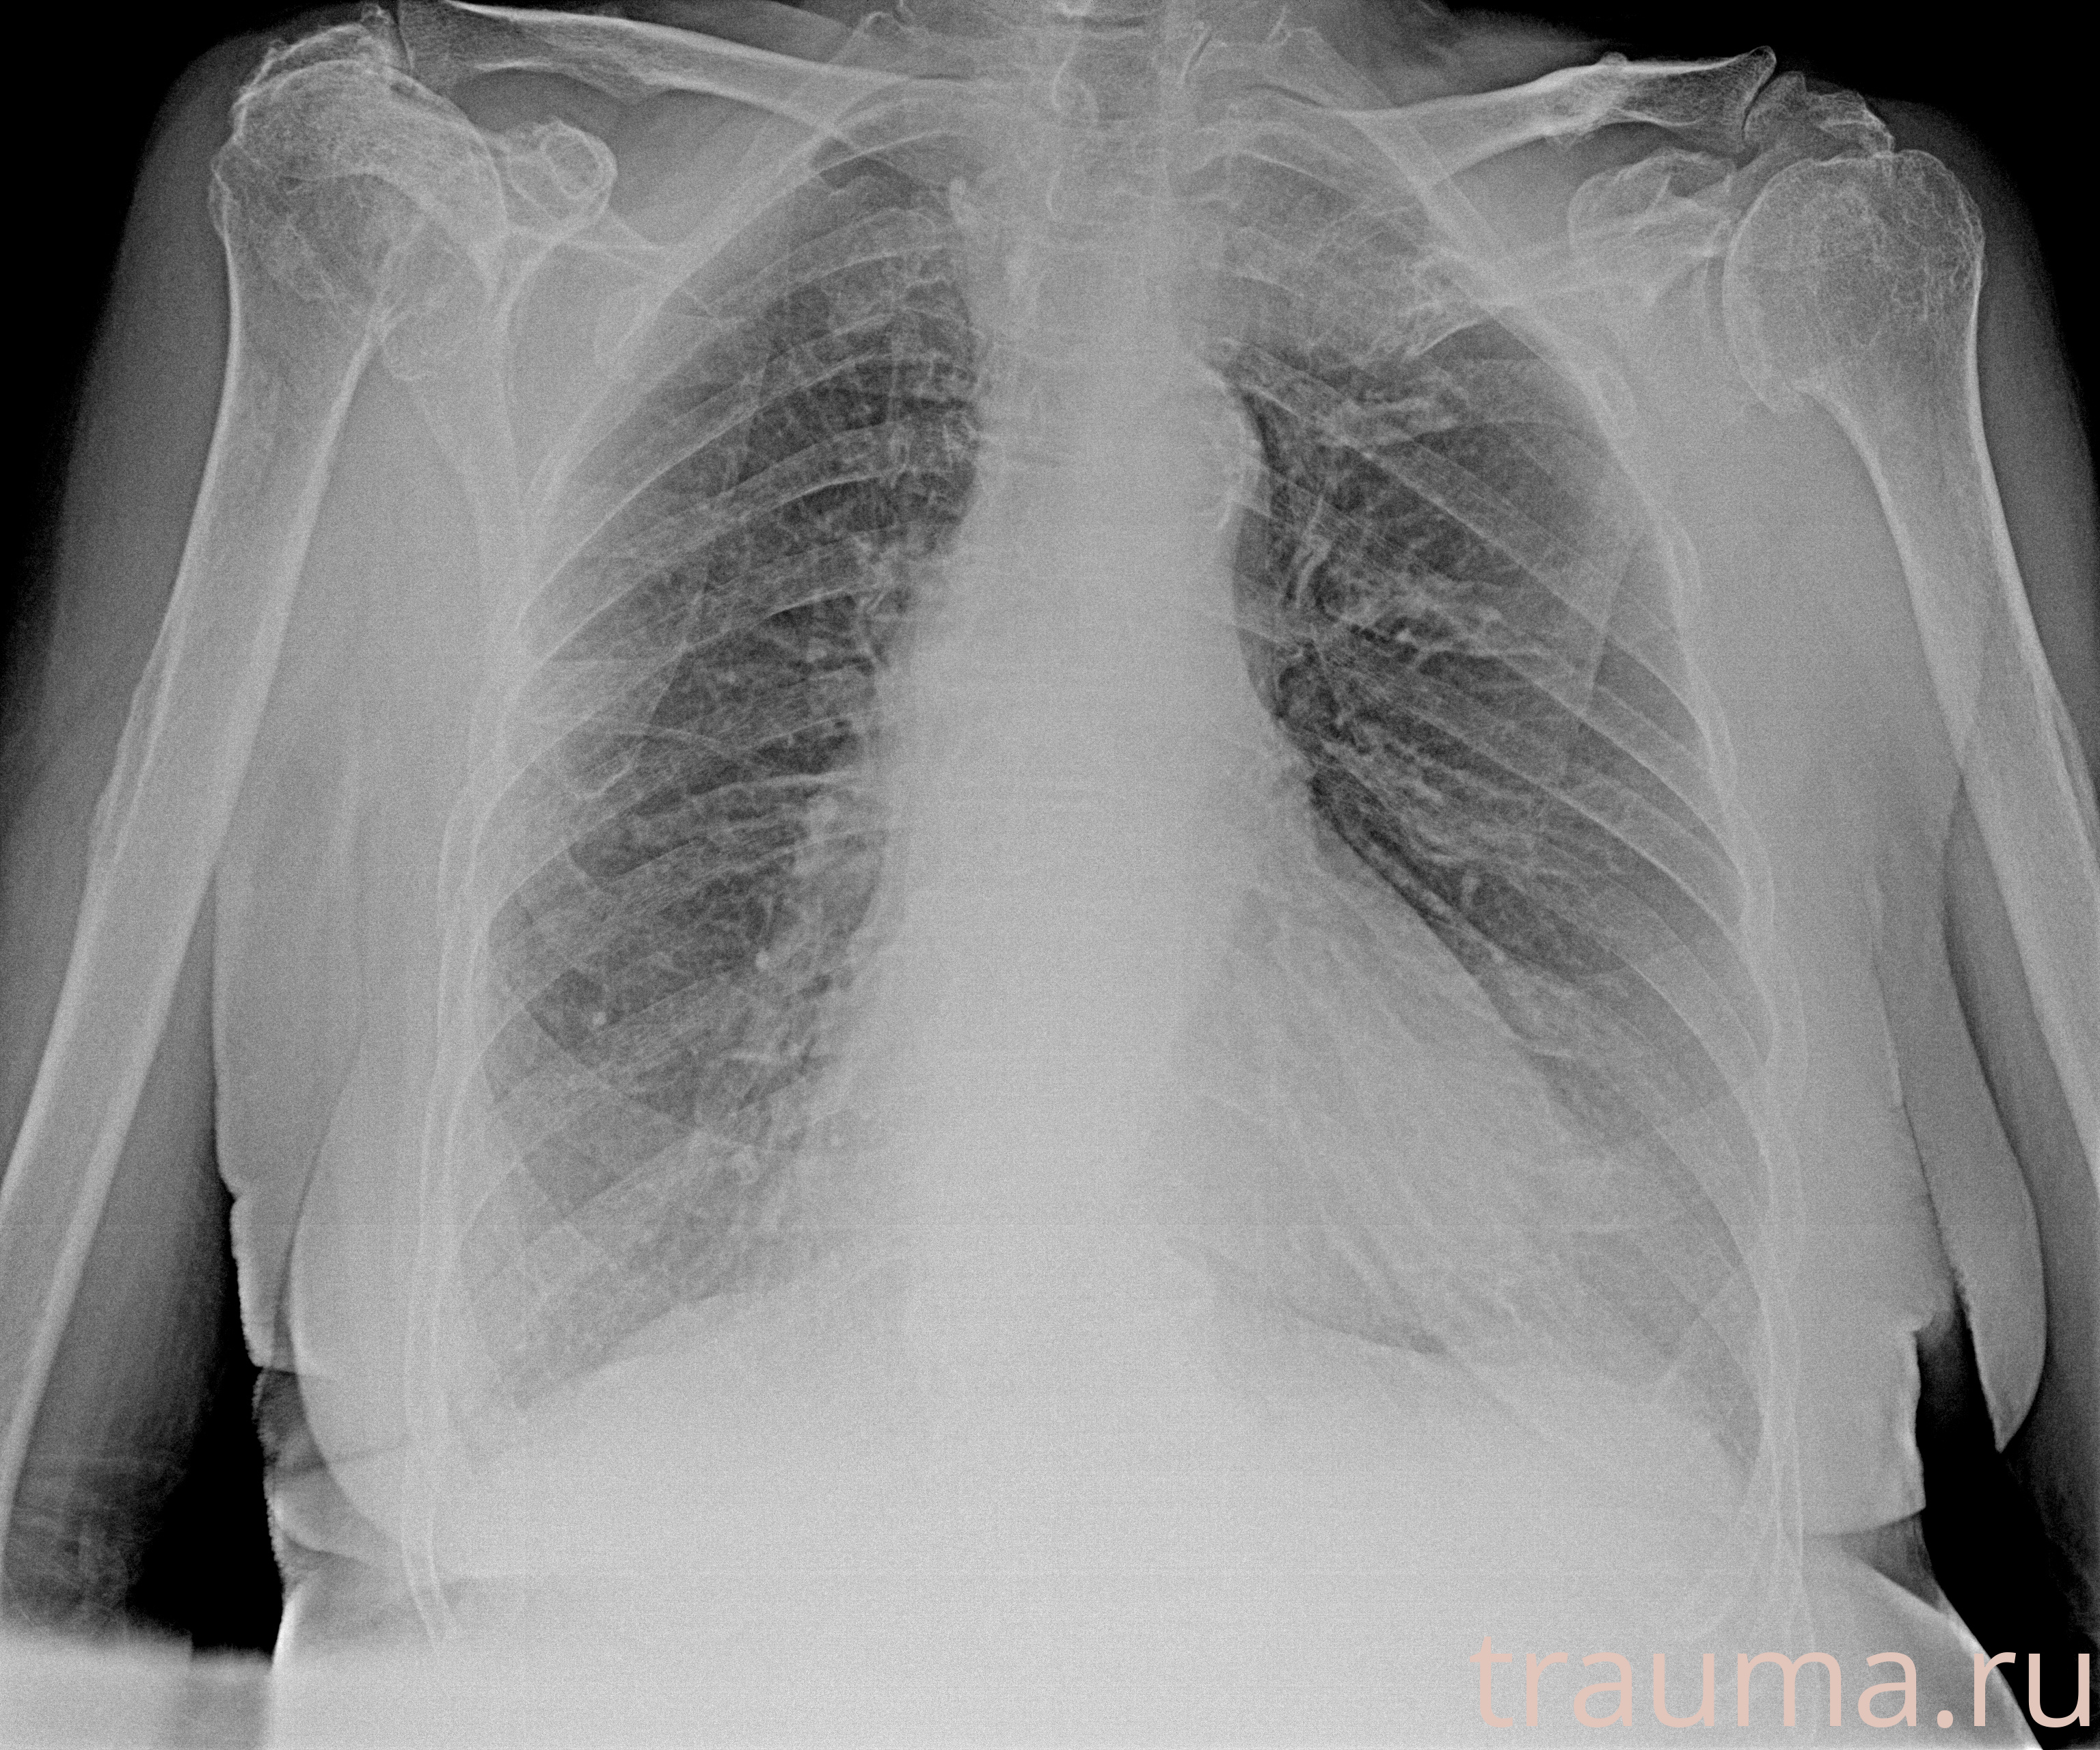

Рентген на дому: по вашему адресу приезжает врач-рентгенолог, травматолог-ортопед с мобильным рентгеновским аппаратом, проводит диагностику травмы или заболевания, делает необходимые рентгенограммы, дает рекомендации по дальнейшему лечению. Получить качественные снимки в домашних условиях возможно благодаря уникальной методике, разработанной МосРентген Центром для института  Склифосовского